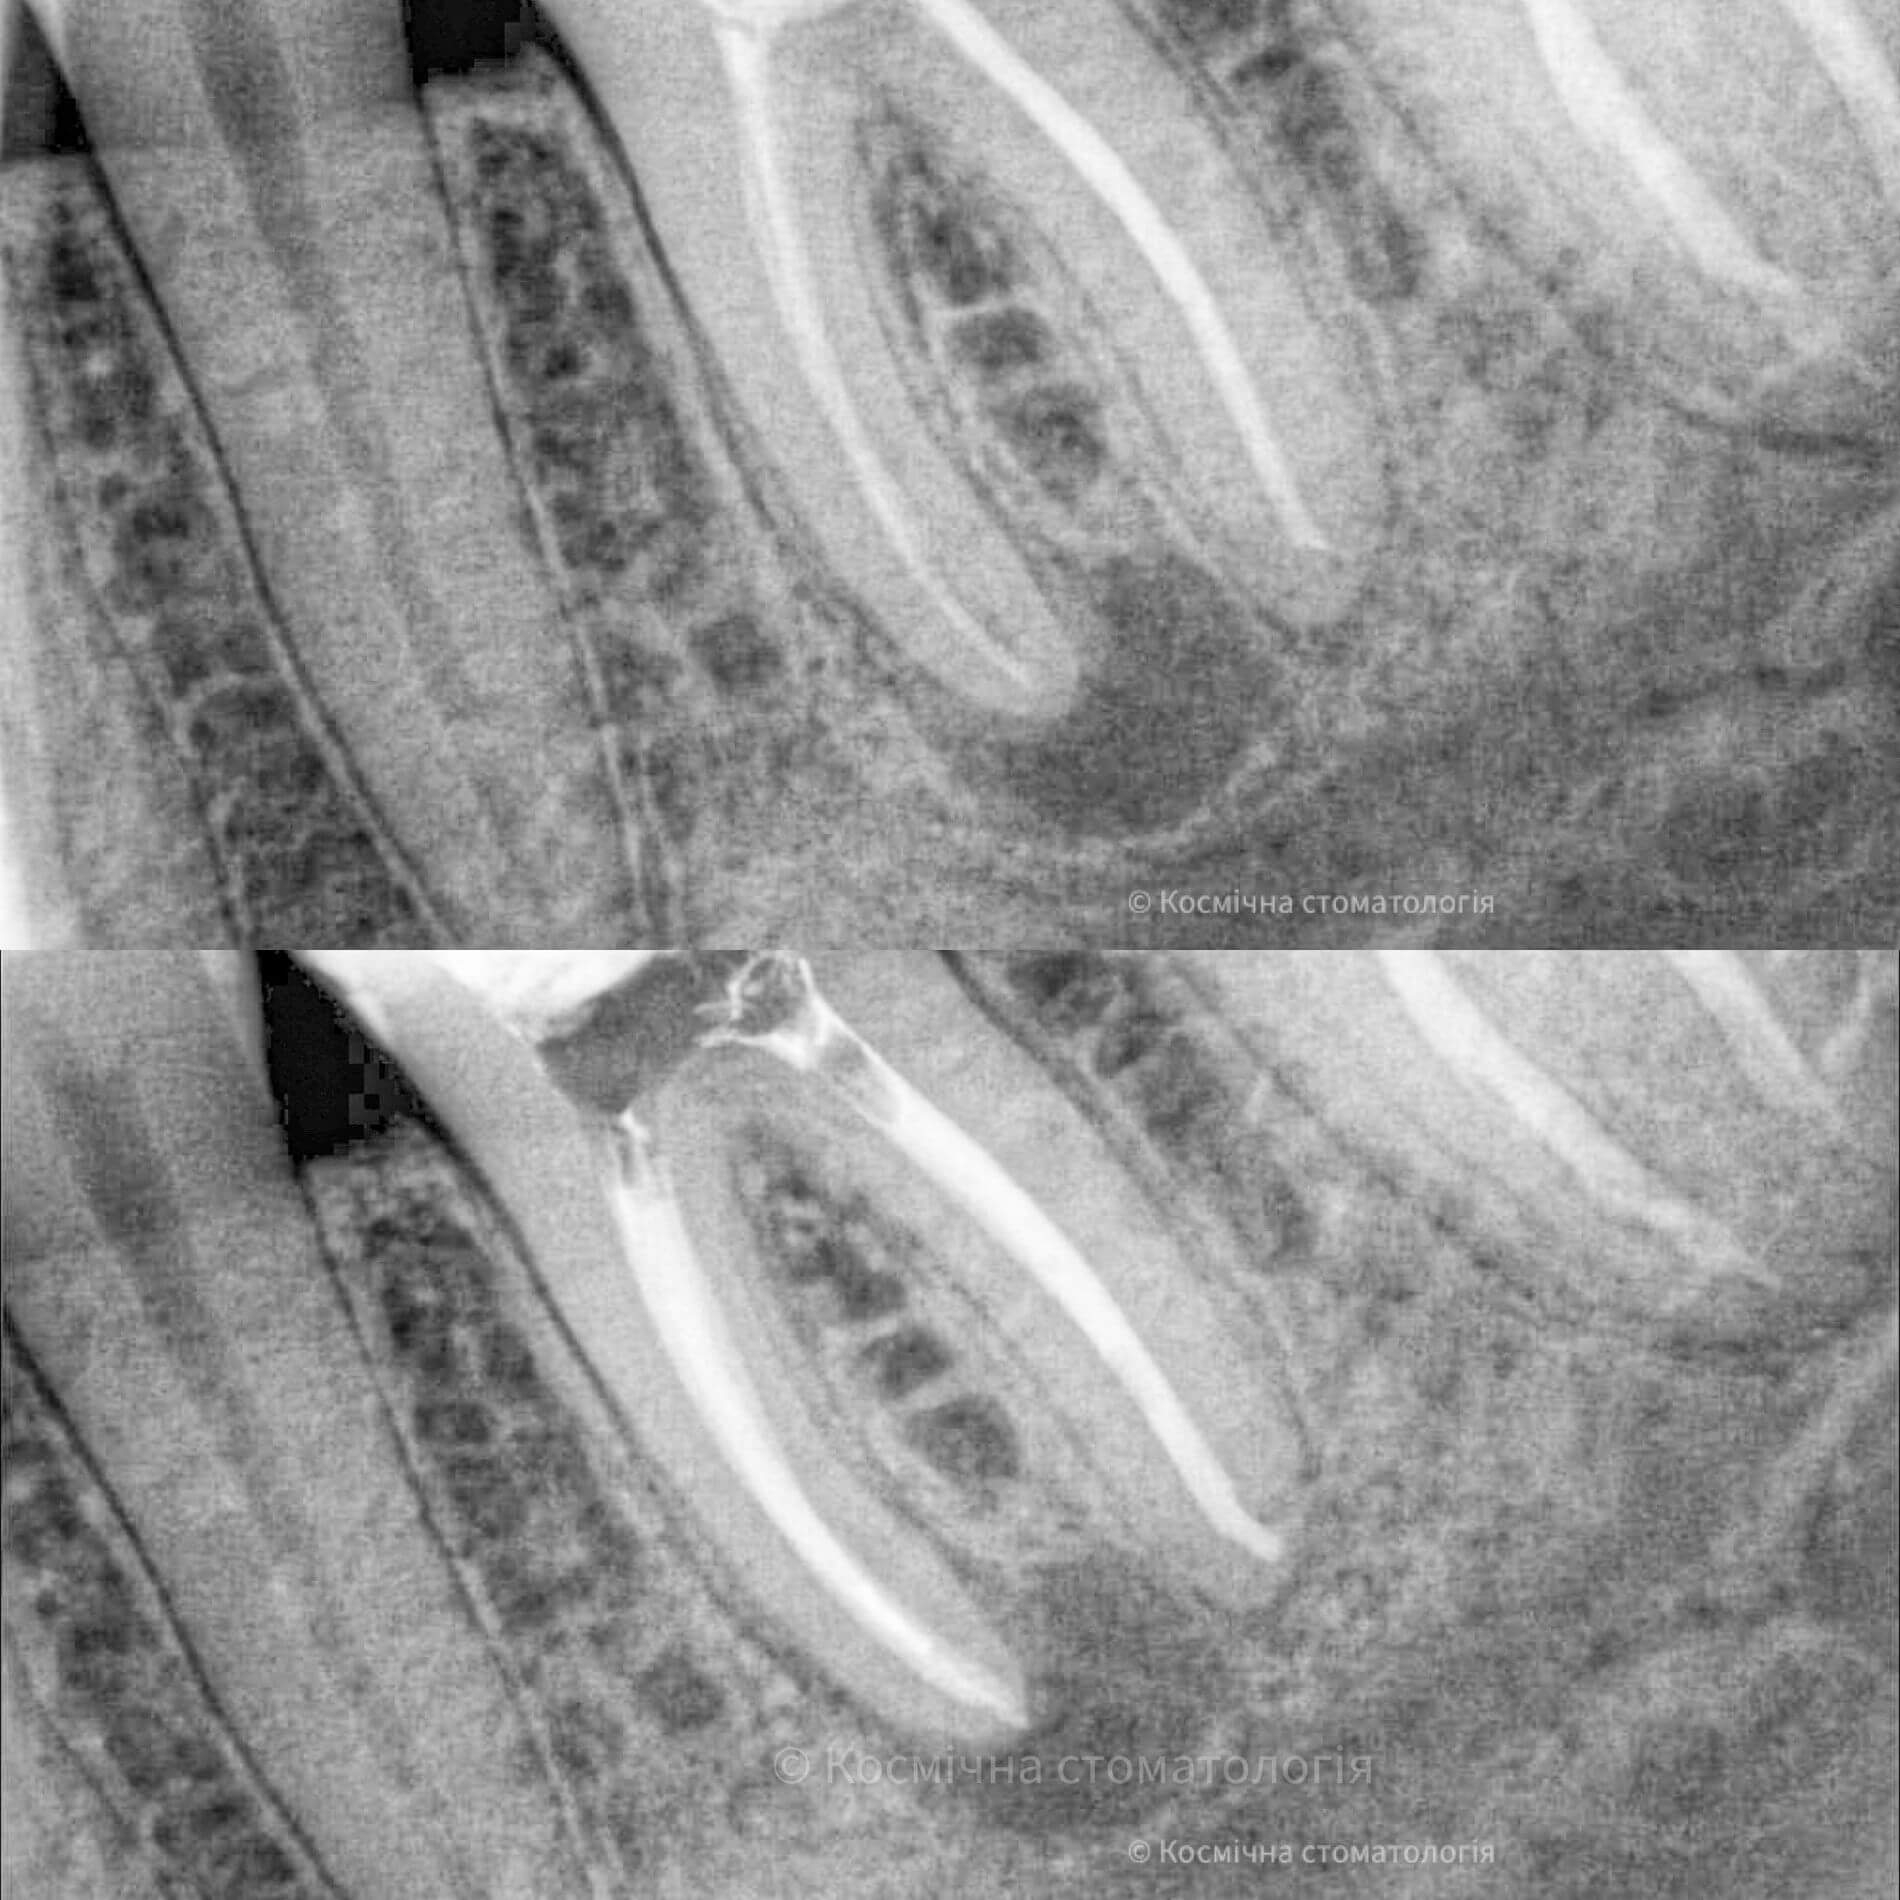

Мы уже говорили, качественное лечение зубных каналов – это довольно сложный и трудоемкий процесс, но с ним с легкостью справится наша космическая команда. Эта процедура затруднена отсутствием полноценного доступа к операционной полости, да еще зубные каналы часто искривлены и очень узкие, что делает невозможным визуальный контроль за проведением процедуры.

Но инновационные технологии и применение рентгенологического контроля выводят лечение каналов зуба во Львове специалистами Космической стоматологии Драганчука на новый межгалактический уровень.

Чтобы провести процедуру лечения и пломбирования каналов, мы в космической стоматологии Драганчука используем оптическое увеличение с помощью микроскопа Carl Zeisse.

Он позволяет вывести изображение на большой экран и масштабировать его, чтобы наша космическая команда могла осуществить все необходимые манипуляции особенно скрупулезно. Благодаря такому оптическому контролю каждого этапа лечения, мы можем оценить его эффективность и предотвратить возникновение осложнений.